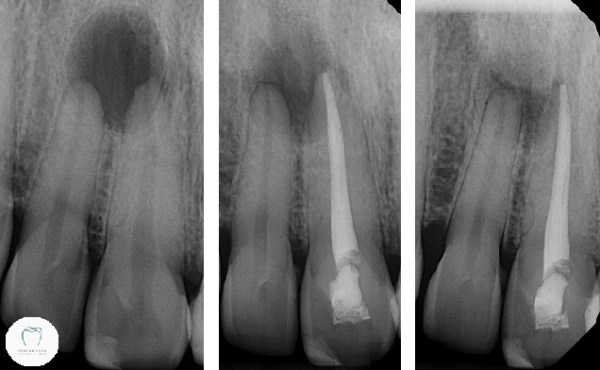

Having cleaned out the dead nerve and completed the root canal treatment in just the central tooth, we wait. Here’s the sequence of x-rays showing what happened over the year:

Well, you should be able to see for yourself what’s happened here. The big dark open hole in the bone has almost completely filled in. It certainly appears that the single root canal treatment is successful. There’s still some risk that I’ll end up having to root treat the other tooth too, but hopefully not. (The patient of course is fully aware of this)